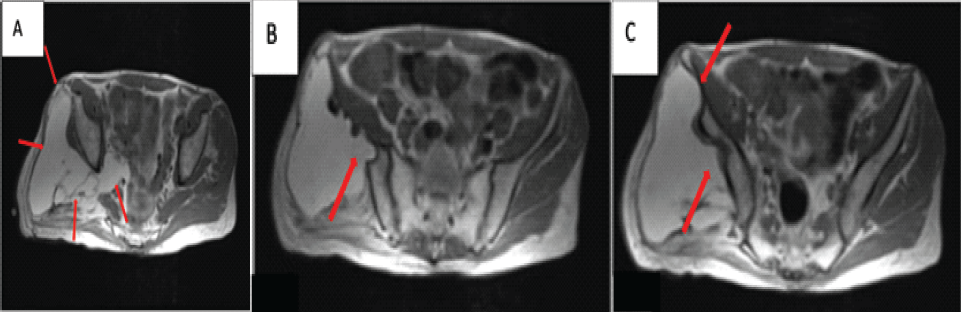

A 68 year-old man presented with a recurrent, non-painful mass in the right buttock. He had two prior resections at outside facilities. The first resection was of an intrapelvic mass performed 27 years before presentation through an anterior approach. The patient reported that this mass was a lipoma but no documentation of the histopathologic evaluation was available for review. The second resection was of a right buttock mass done 1 year before presentation through a posterior approach. Histopathologic interpretation of this mass at the outside hospital was that of a lipoma. Since the second resection, he noted a slow return of the mass along with pain in his right buttock that was associated with prolonged periods of sitting. On physical examination, there was a fullness of the right buttock with an apparent soft tissue mass that was soft and non-mobile. MRI demonstrated a mass that was hyperintense on T1 and T2 pulse sequences consistent with a lipomatous mass. The mass was predominantly in the buttock but extended through the sciatic notch into the retroperitoneal space (Fig. 2a). The majority of the mass appeared to be benign fat with some smaller areas with increased stranding. The mass abutted the posterior aspect of the ilium and appeared to have eroded through the posterior cortex in several places (Fig. 2b and c). There were no changes in the marrow adjacent to the erosions into the ilium. The changes in the ilium were better demonstrated on the CT scan with scalloping of the posterior ilium adjacent to the mass (Fig. 3a and b).

Figure 2: Case 2 magnetic resonance imaging T1-weighted imaging findings – axial (a) demonstrates a large fatty mass with some internal septations that extend through the sciatic notch into the retroperitoneal space (red arrow). (b and c) Demonstrates a large fatty mass that abuts the posterior aspect of the ilium which has eroded the posterior cortex in several places (red arrow).

Figure 3: Case 2 computed tomography imaging findings – axial. (a and b) Demonstrates scalloping of the posterior cortex of the ilium by a large low attenuation mass (red arrow).